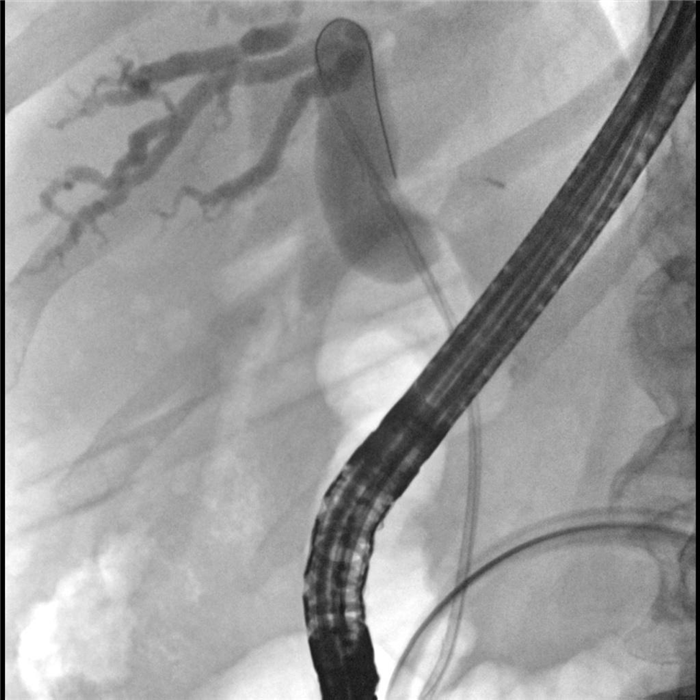

Cтентирование пластиковым стентом

Состояние после вклинения камня и образования супрапапиллярного свища